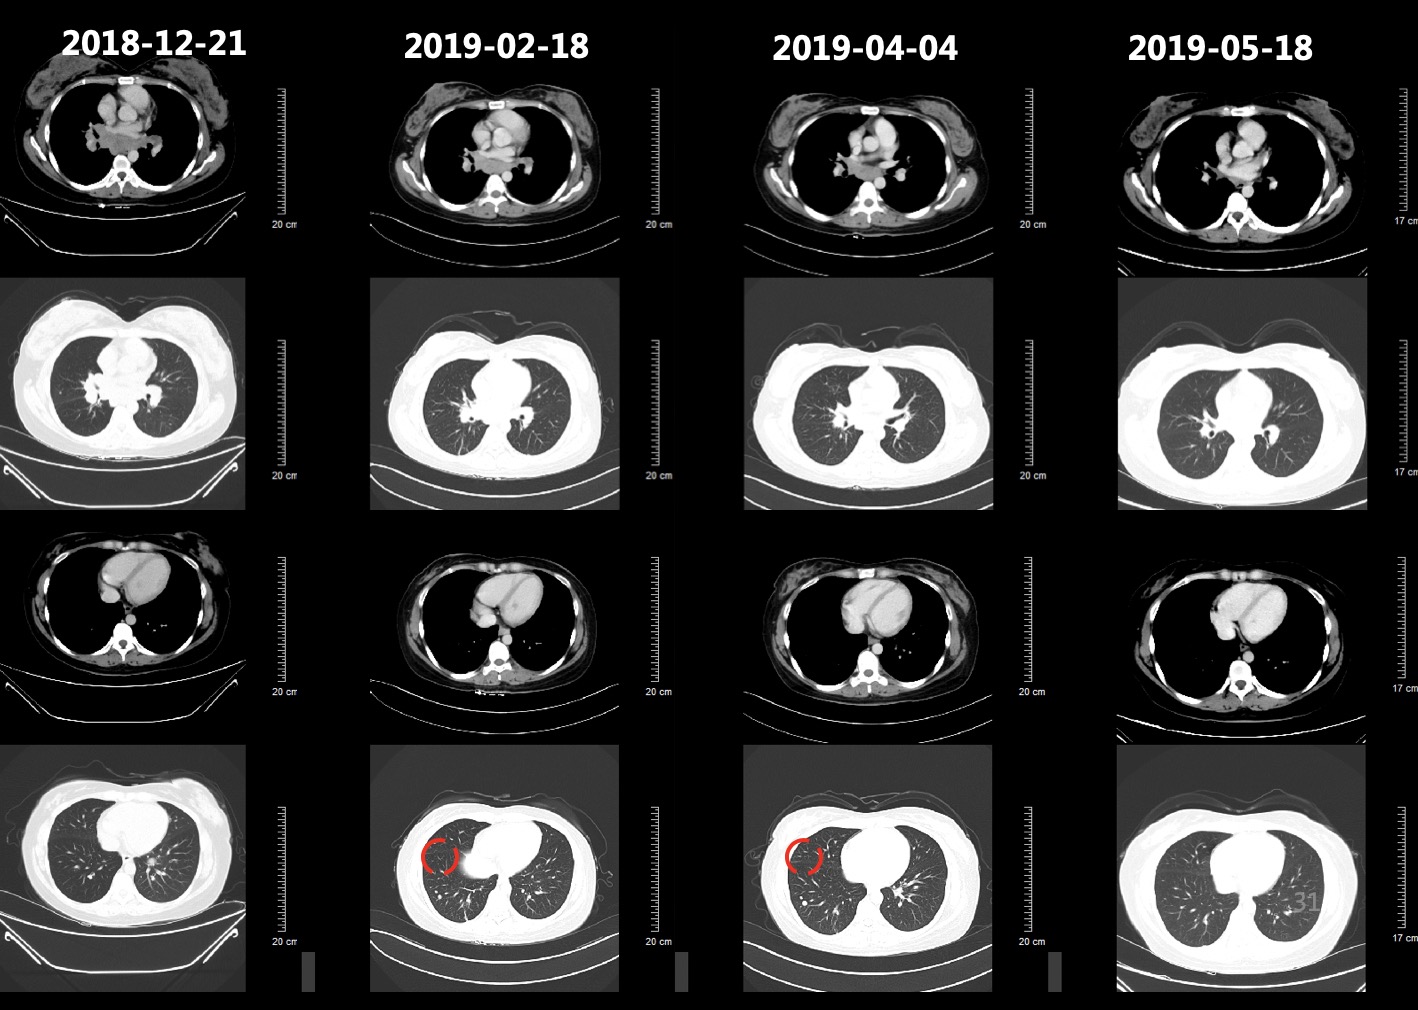

患者于2018-12-26、2019-01-19分别行第1-2周期TC方案(紫杉醇脂质体+卡铂,每3周1次),患者基线和化疗后肿瘤标志物变化如图3所示,肺和肝脏病灶变化影像如图4所示,2019-02-18复查CT提示肺部病灶稳定(缩小),肝脏病灶增多增大,总体疗效评价疾病进展(PD)。

图4 患者基线和化疗后肺部病灶和肝脏病灶对比影像,肺部病灶缩小,肝脏病灶增多增大

2019-02-19、2019-03-14行二线贝伐珠单抗+多西他赛化疗(贝伐珠单抗+多西他赛,每3周1次)。2019-03患者开始出现腰部疼痛,考虑为L1椎体骨转移导致,2019-03-19开始行腰骶部局部放疗,2019-04-04复查CT结果如图5所示,肺部病灶稳定(部分缩小),肝脏病灶增多增大、T9-T12椎体新发转移瘤,总体疗效评价(PD)。

图5 2019-04-04复查胸腹部CT结果影像,结果显示肺部病灶稳定(部分缩小),肝脏病灶增多增大、T9-T12椎体新发转移瘤

患者初治时行PD-L1(22C3)检测提示PD-L1高表达为95%,故建议患者行三线免疫治疗。由于药物可及性,患者综合考虑后,选择信迪利单抗。患者于2019-04-04、2019-04-26、2019-05-18分别行第1~3周期免疫联合化疗三线方案(信迪利单抗+白蛋白紫杉醇 ,每3周1次)。2019-05-18复查肺部CT如图6所示,2019-05-18复查CT:肺部病灶较前明显缩小,阻塞性肺炎较前好转、肝脏病灶较前明显缩小。T2、T9-L2椎体及L2左侧附件多发骨转移同前。

图6 2019-05-18复查胸腹部CT提示肺部病灶较前明显缩小,阻塞性肺炎较前好转、肝脏病灶较前明显缩小。T2、T9-L2椎体及L2左侧附件多发骨转移基本同前